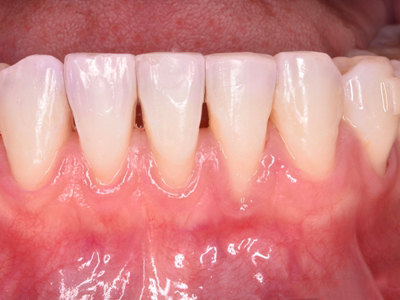

牙龈退缩牙龈萎缩露出牙根图

牙龈退缩发作于上排尖牙和磨牙处,导致牙根暴露在外,伴有牙齿松动、口臭、牙根面敏感等症状,是由于刷牙不当、牙周炎等因素引起。